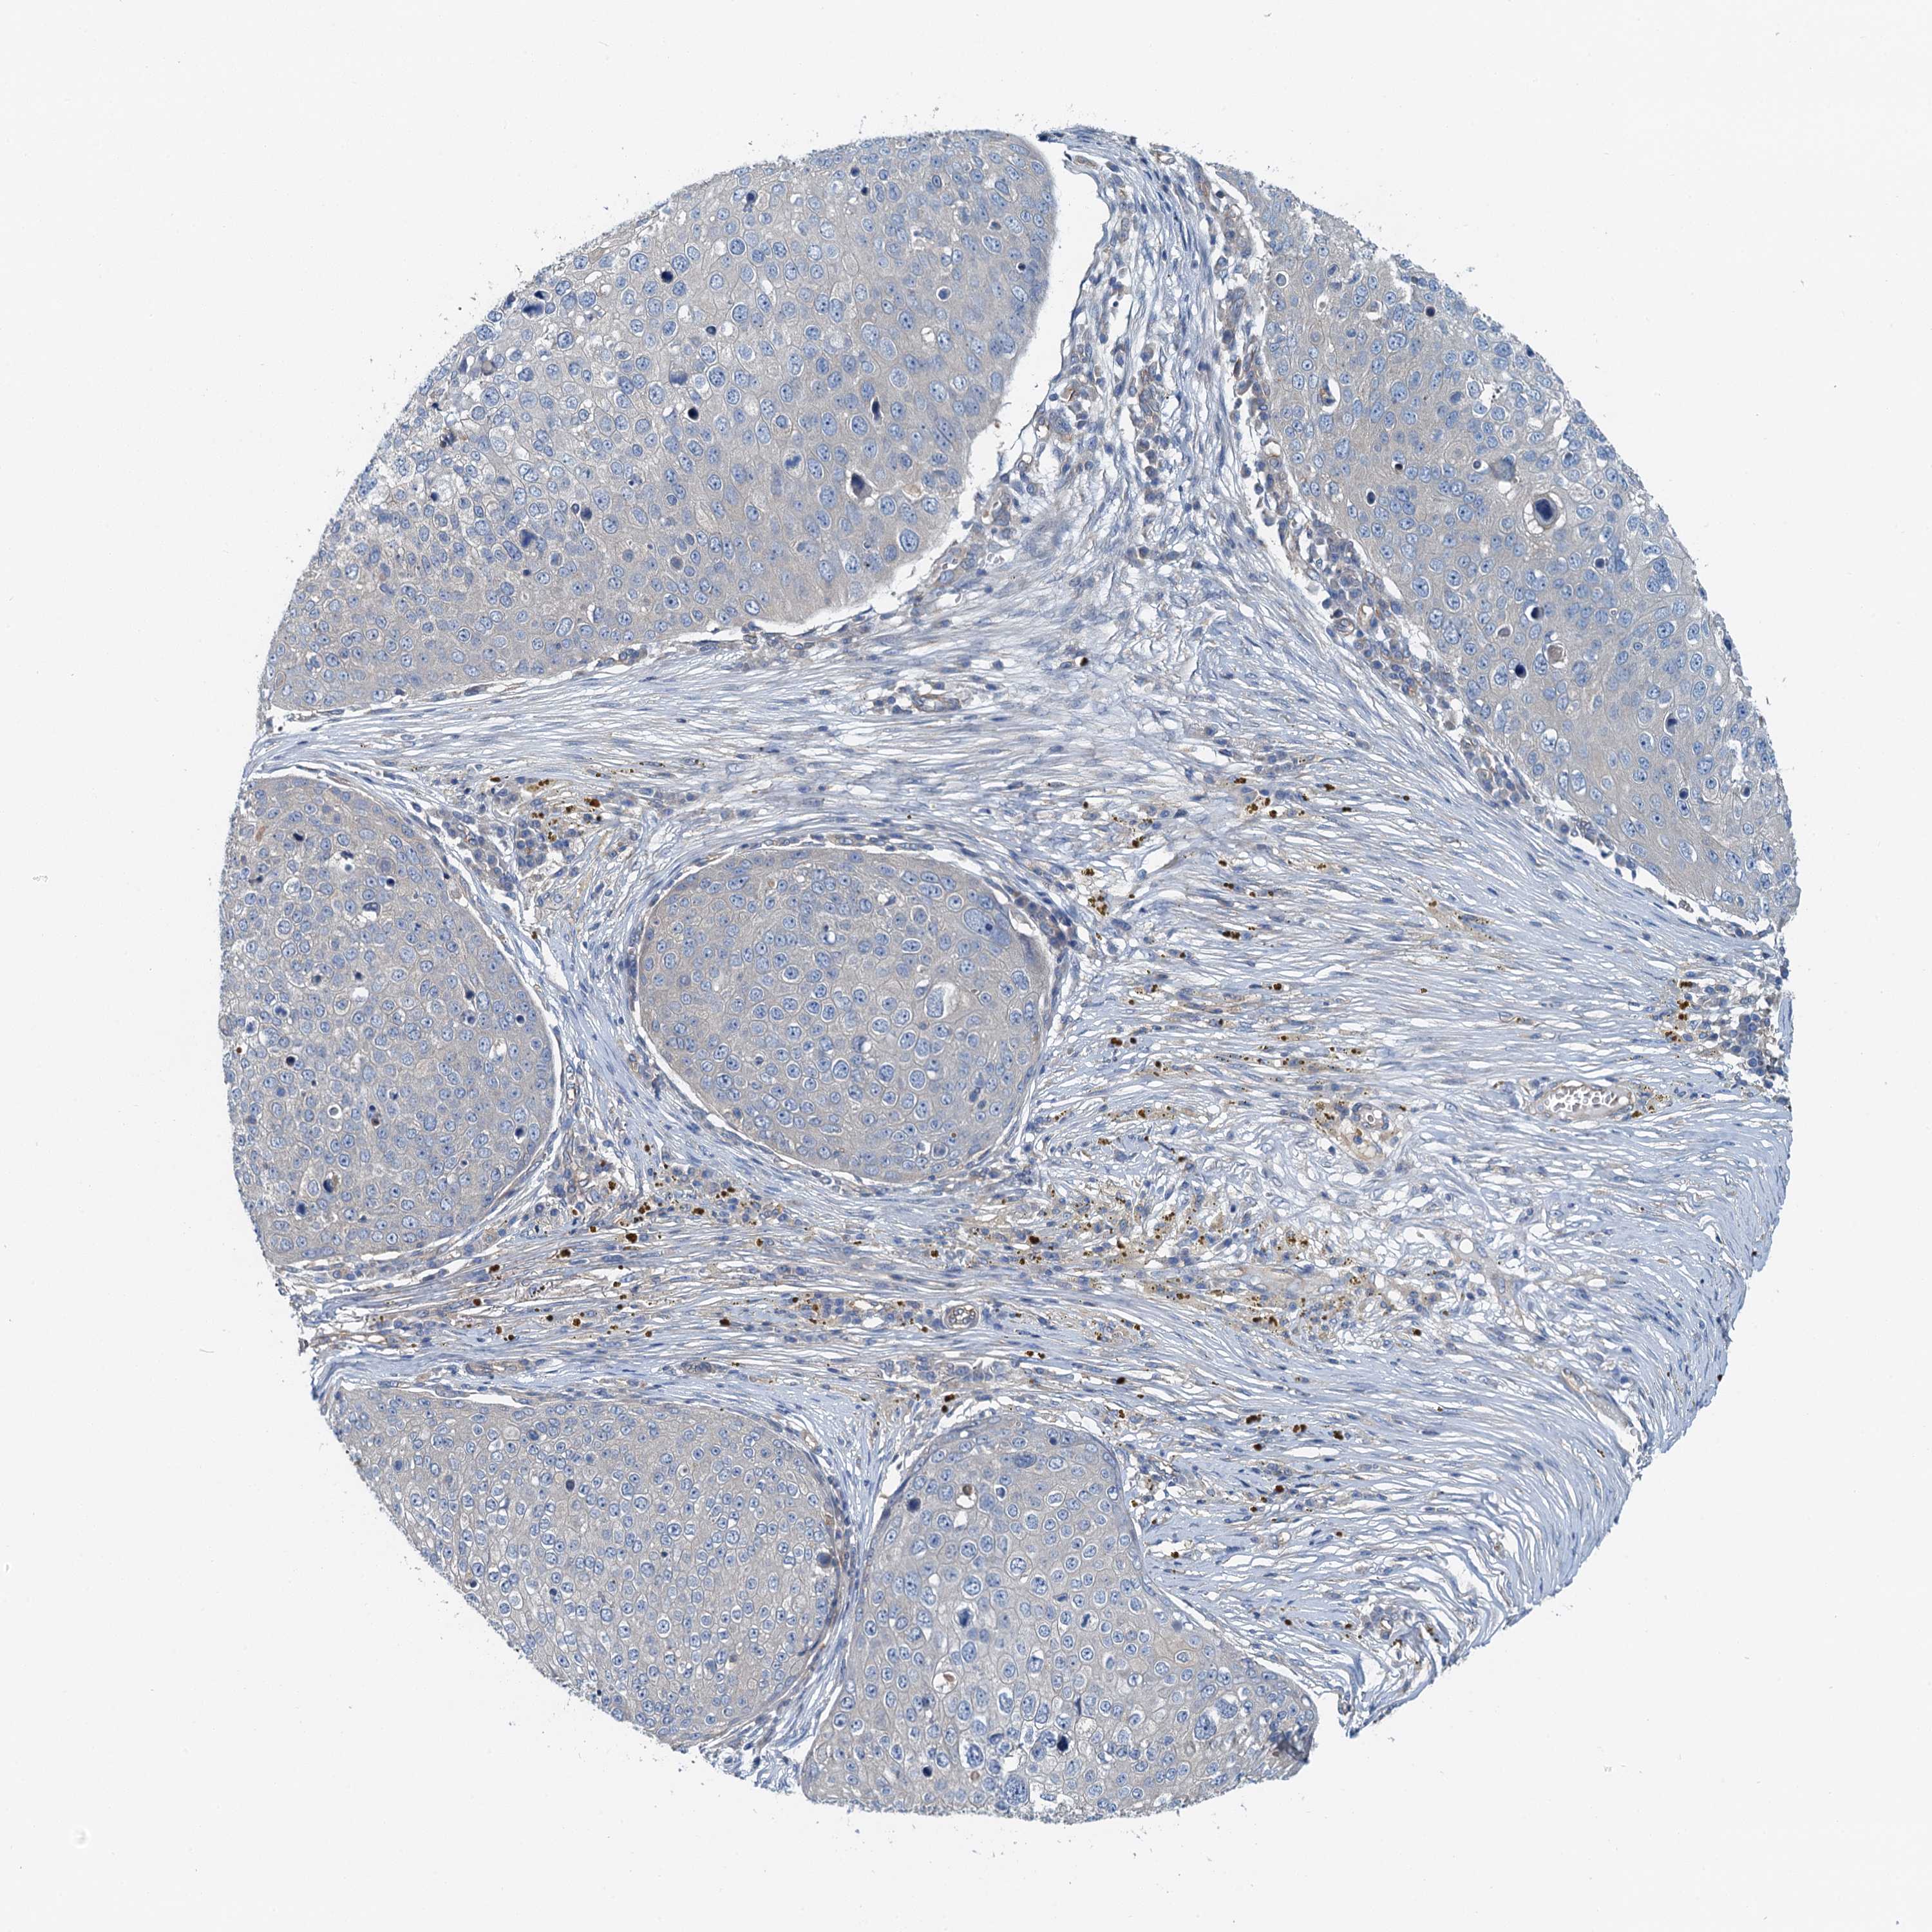

Basal cell and squamous cell cancer

SKIN CANCER - Protein expressioni

A mouse-over function shows sample information and annotation data. Click on an image to view it in a full screen mode. Samples can be filtered based on level of antibody staining by selecting one or several of the following categories: high, medium, low and not detected. The assay and annotation is described here.

Each image is clickable and will lead to virtual microscopy that enables deeper exploration of all samples and also displays staining intensity scores, fraction scores and subcellular localization as well as patient and tissue information for each sample.

Antibody HPA041000

Staining

High

Medium

Low

Not detected

Intensity

Strong

Moderate

Weak

Negative

Quantity

>75%

75%-25%

<25%

None

Location

Nuclear

Cytoplasmic/membranous

Cytoplasmic/membranous,nuclear

Squamous cell carcinoma, metastatic, NOS

Squamous cell carcinoma, NOS